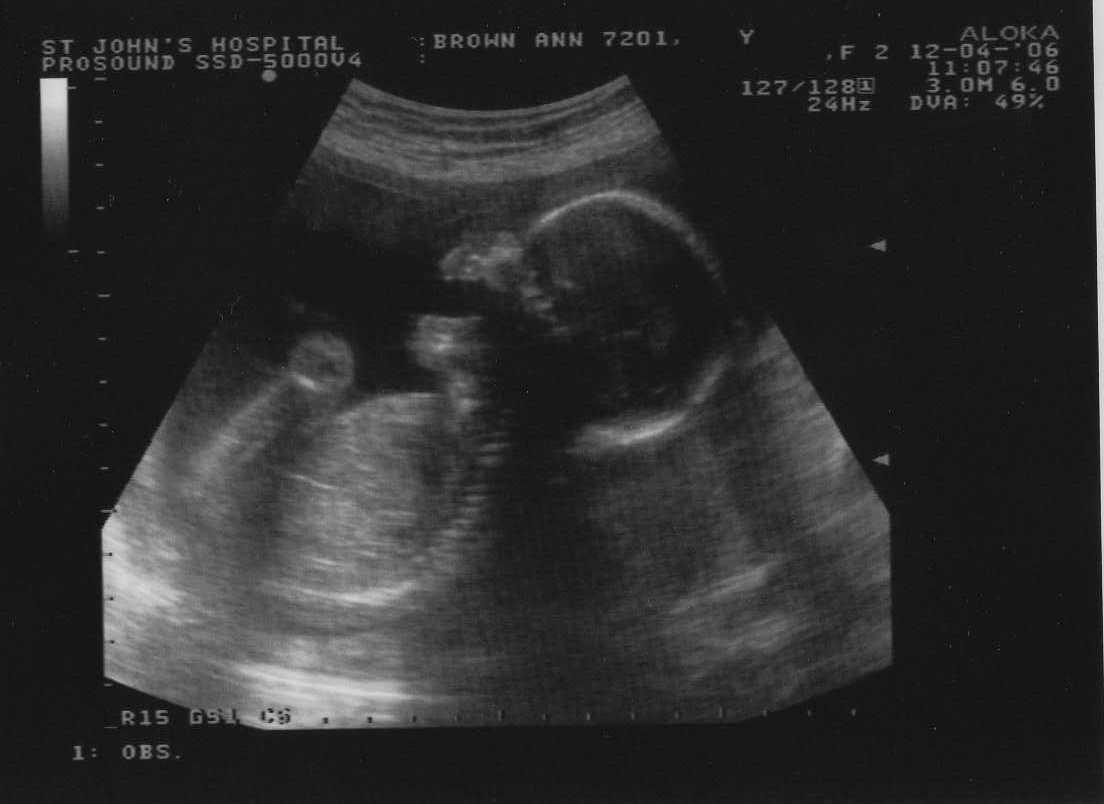

12th April 2006 (20 weeks) ... an ante natal yawn